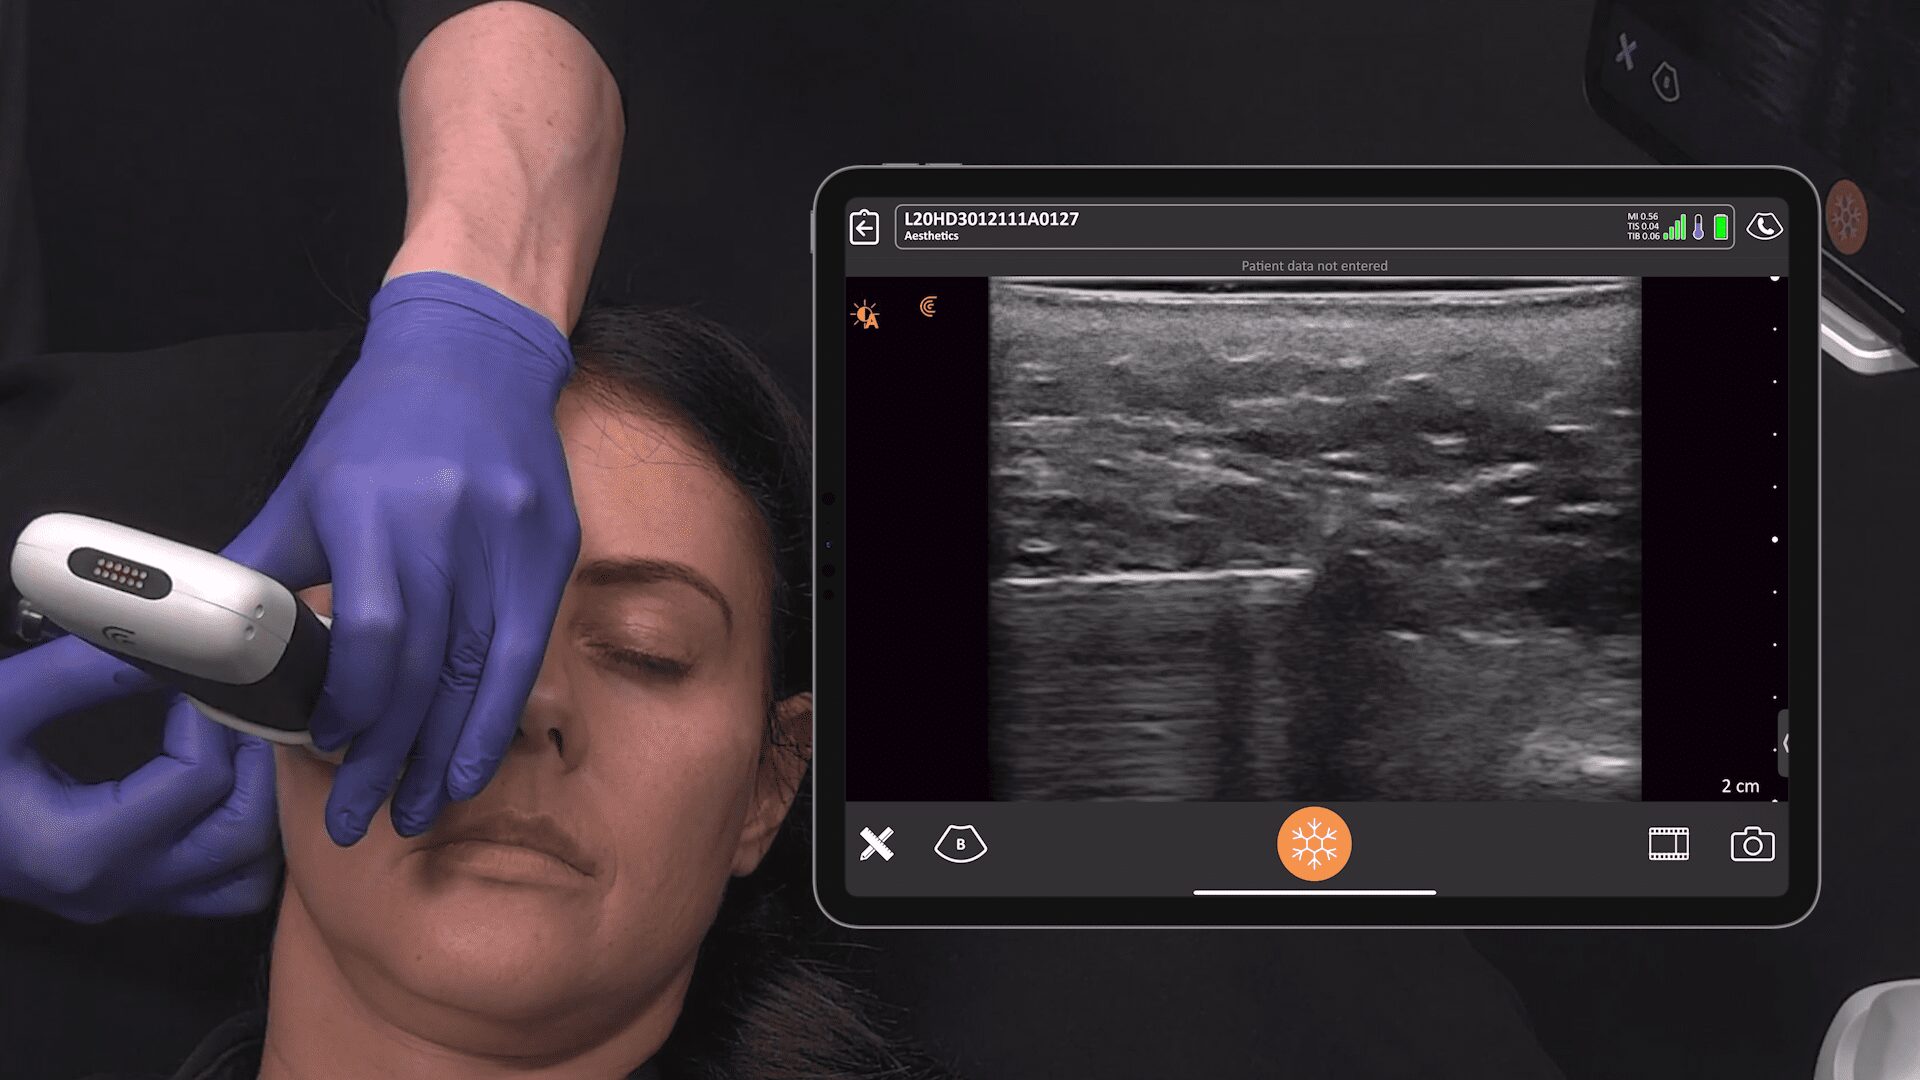

Setting Up for the Exam

This is my setup in a regular exam room. I’m using the new Clarius L7 HD device with an iPad. I bought a bracket online for under $100 and hooked it to the back of the chair so that I can touch the screen if I need to. But I usually use the buttons on the device instead of touching the screen. I’ve programmed the bottom button to freeze the image and the top button to save the image. To record a video, I push the bottom button and a little icon appears that looks like a movie camera – it will take a 10-second video and stores it on the iPad and then upload it to the Cloud at the end of the exam. It’s very simple to do from the room.